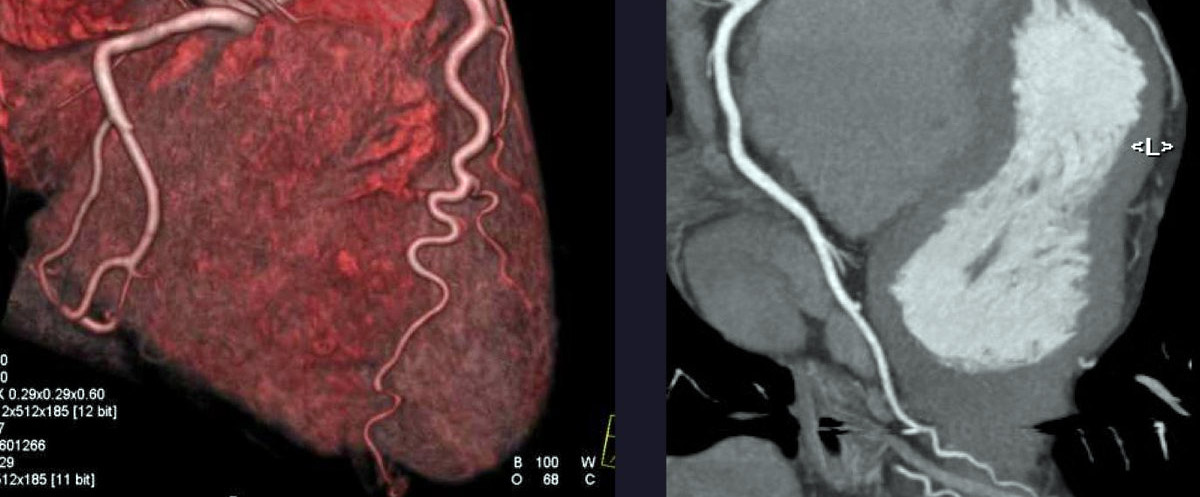

Koroner BT anjiyografi doğru seçilmiş hasta gruplarında altın standart yöntem olan invaziv koroner kateter anjiyografi ile uyumlu bir seçenek olarak yerini genişletmektedir.

Çözünürlüğü yüksek, komplikasyon riski ve morbiditesi düşük hızlı bir yöntemdir. Konvansiyonel anjiyografi ile görülemeyen bazı detayların ve damar içindeki plakların yapısının da görülebilmesine olanak tanır. Örneğin; miyokard enfarktüsü ile ani ölümlere yol açabilen yumuşak plaklar ile kalsifiye plakların ayırıcı tanısı yapılabilir, stenozun yani darlığın derecesi belirlenebilir. Tüm bunlar merkezimizde de bulunan yeni nesil ve en güncel teknoloji cihaz sayesinde çok düşük radyasyon dozları ile gerçekleşir.

Bu alanda yapılmış yayınlara göre, böyle bir cihaz ile yapılan koroner BT anjiyografinin sensitivitesi yaklaşık %99, pozitif öngörü değeri %92 , negatif öngörü değeri %95 olmak üzere oldukça yüksektir. Bu özellikleriyle koroner kateter anjiyografiye güçlü bir alternatif ve tanıda yeni altın standart olma yolunda ilerlemektedir. Koroner arter stenozlarını (darlıklarını) dışlayabilmedeki gücü sayesinde invaziv kateter koroner anjiyografi planlanmış fakat düşük-orta seviyede koroner arter hastalığı olasılığı bulunan hastalarda tartışılmayacak üstünlüğe sahiptir. Ancak klinik durumu tedavi gerektirecek ölçüde bir darlık varlığını düşündüren hastalarda kateter koroner anjiyografi anında girişim ile tedavi seçeneğini de sunduğundan öncelikli yerini korumaktadır.

Koroner BT anjiyogafi yapılırken eşzamanlı pulmoner arterler, torasik aorta ve diğer intra-torasik yapılar da görüntülenebildiğinden akut koroner sendrom ile karışabilen durumların ayırıcı tanısı da yapılabilir. Damarlardaki plakların daha erken görülebilmesini ve yaşamı tehdit eden yumuşak plaklar ile kalsifiye plakların ayırt edilmesini sağlar. Koroner by-pass greft operasyonu gecirenlerde ve stent uygulanmis hastalarda non-invaziv olmasiyla tercih edilebilir. Ayrıca klostrofobi, pacemaker vb nedenlerle kardiyak MRI için uygun olmayan hastalar için yine güçlü bir seçenektir.